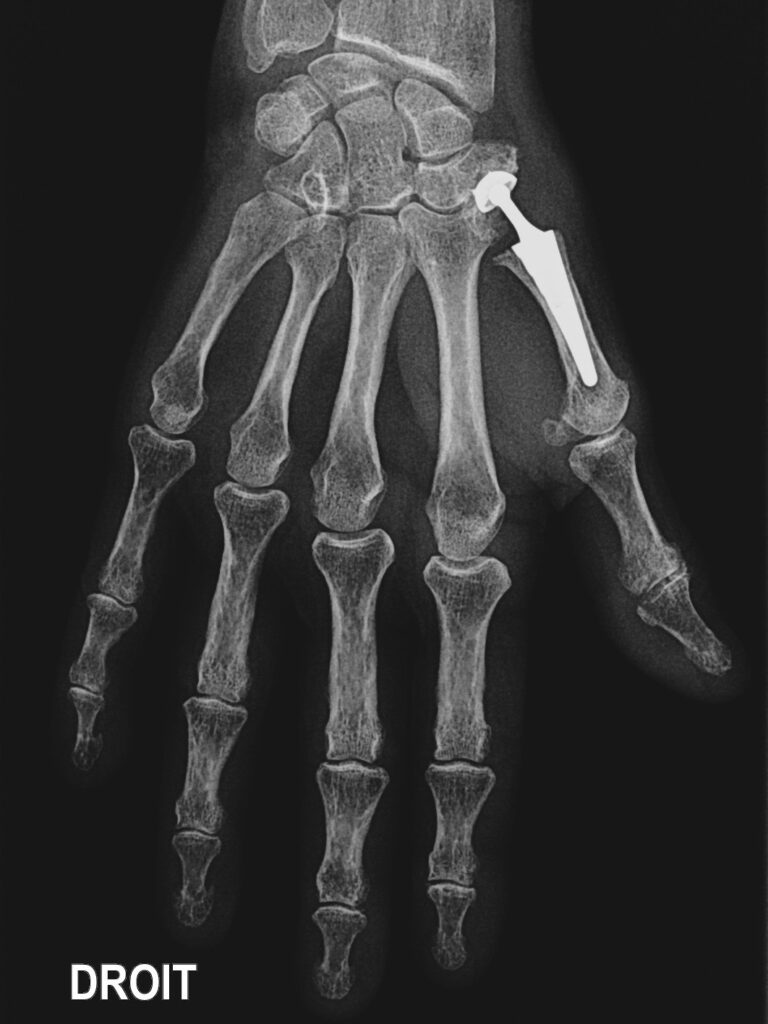

La chirurgie n’est envisagée qu’après échec du traitement médical. Certains proposent, la mise en place d’une prothèse en plastique ou d’une prothèse articulée en métal. D’autres préfèrent enlever le trapèze et stabiliser le pouce avec un tendon de voisinage. Dans certains cas particuliers on peut proposer de bloquer l’articulation (arthrodèse). Réalisées sous anesthésie loco-régionale, elles peuvent être pratiquées à l’occasion d’une hospitalisation de courte durée (ambulatoire). Toutes ces interventions nécessitent une immobilisation plus ou moins longue (15 jours à 6 semaines). Les interventions qui remplacent le trapèze ont une récupération souvent longue. Ces interventions ne redonnent jamais un pouce normal et ne permettent pas de récupérer la force de serrage complète de la main, malgré une rééducation souvent longue.

- Les prothèses articulaires sont fabriquées à partir de matériaux qui vont s’user avec le temps. Cette usure est plus ou moins rapide en fonction de votre activité. Les prothèses en métal sous souvent fixées avec du ciment qui peut se décoller de l’os avec le temps (descellement).

L’usure ou le descellement peuvent conduire à une réintervention.